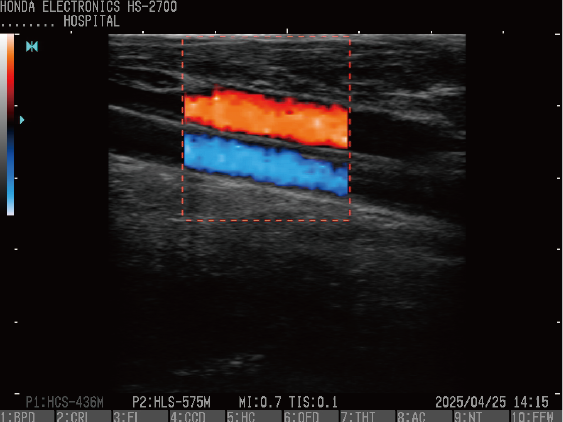

ドプラモード

HS-2700はCFM(カラーフローマッピング)、PD(パワードプラ)、PW(パルスウェーブドプラ)3種類のドプラ機能を持っております。

CFM(カラーフローマッピング)

プローブ:HLS-575M